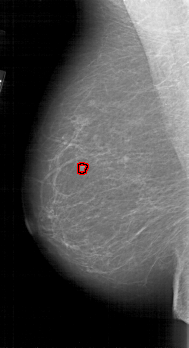

A_1812_1.LEFT_CC

LEFT_CC LINES 5416 PIXELS_PER_LINE 2716 BITS_PER_PIXEL 12 RESOLUTION 43.5 OVERLAY

FILE: A_1812_1.LEFT_CC.OVERLAY

TOTAL_ABNORMALITIES 1

ABNORMALITY 1

LESION_TYPE MASS SHAPE LOBULATED MARGINS MICROLOBULATED

ASSESSMENT 4

SUBTLETY 3

PATHOLOGY BENIGN

TOTAL_OUTLINES 1